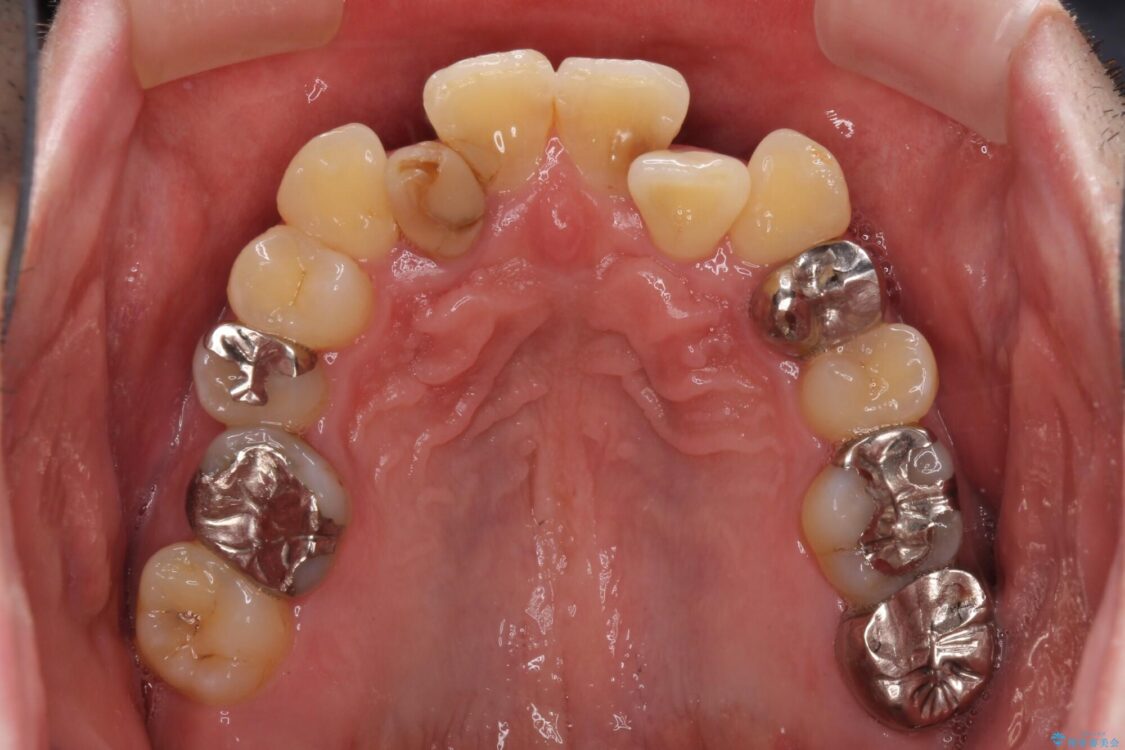

矯正治療でインプラント埋入を行い、矯正治療後に気になる前歯と合わせてオールセラミッククラウンによる補綴治療を行うこととしました。

治療後について

骨造成や歯肉移植など、治癒期間の長い処置を必要としたため治療期間は長くなりましたが、安定した咬み合わせと整った歯列となり、患者様には大変満足していただきました。

治療後

• 割れてしまった奥歯とデコボコの前歯 矯正治療とインプラント治療 治療後画像